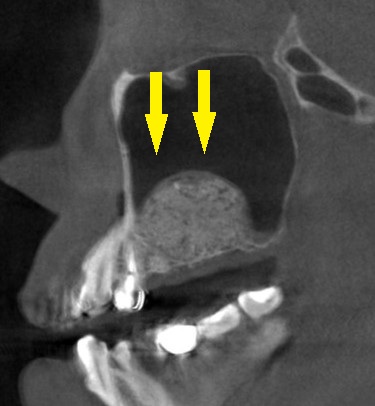

それでも、患者様の強い希望がありましたので、他に方法はないと考え、まずサイナスリフトという、人工骨を上顎の空洞部分に填入して骨を増やす手術を、本日施行しました。

下の写真、下段右が、手術後のCTです。